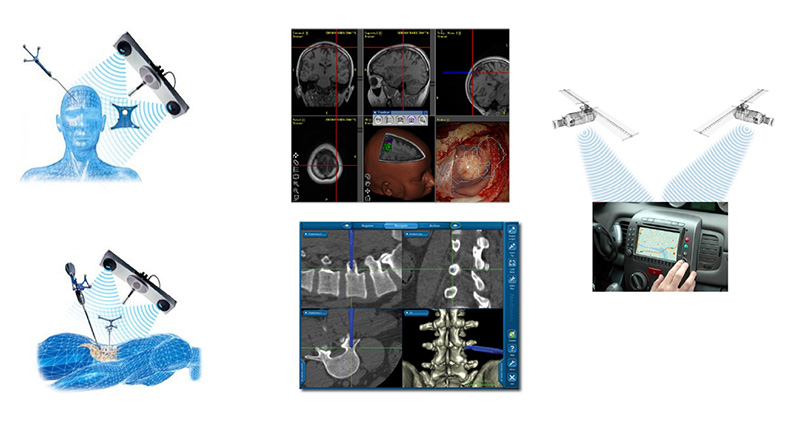

Ο τρόπος λειτουργίας του συστήματος είναι ο εξής: όπως οι δορυφόροι ανιχνεύουν τη θέση της μονάδας GPS στο αυτοκίνητό μας και το σύστημα πλοήγησης επιδεικνύει τη θέση του αυτοκινήτου στους τρέχοντες χάρτες, έτσι και μια κάμερα μέσα στο χειρουργείο ανιχνεύει τη θέση των χειρουργικών εργαλείων. Η θέση αυτή εμφανίζεται στην οθόνη του συστήματος, πάντα σε πραγματικό χρόνο, σε άμεση σχέση με την πραγματική ανατομία του ασθενούς (οπτική τεχνολογία εντοπισμού).

Τη θέση της κάμερας αντικαθιστά ένας πομπός. Ο πομπός παράγει ένα ηλεκτρομαγνητικό πεδίο περιμετρικά του ασθενούς και οτιδήποτε μπαίνει στα όρια του πεδίου αναγνωρίζεται αυτόματα από το σύστημα (ηλεκτρομαγνητική τεχνολογία εντοπισμού). Μικροσκοπικοί αισθητήρες προσαρμοσμένοι πάνω στα εργαλεία του χειρουργού αναγνωρίζονται και δίνουν στίγμα μέσα στο πεδίο. Το στίγμα αυτό δίνει μια συνεχή και μεγάλης ακρίβειας πληροφορία στο χειρουργό σχετικά με τη θέση των εργαλείων του και την ανατομία του ασθενούς.

Τα συστήματα χειρουργικής πλοήγησης βρίσκονται στη χειρουργική αίθουσα και χρησιμοποιούν είτε οπτική, είτε ηλεκτρομαγνητική τεχνολογία εντοπισμού, ενώ αποτελούνται, αντίστοιχα, από την ειδική κάμερα ή τον πομπό, την υπολογιστική μονάδα με το λογισμικό, την οθόνη και τα ειδικά εργαλεία πλοήγησης, καθώς και adaptors για την αναγνώριση κοινών χειρουργικών εργαλείων από το σύστημα.

Η ειδική κάμερα-πομπός αναγνωρίζει και εντοπίζει τη θέση των κινούμενων εργαλείων, διασταυρώνοντας τα αντίστοιχα σήματα (ανάκλαση σφαιρών στην οπτική τεχνολογία, στίγμα σήματος στον χώρο στην ηλεκτρομαγνητική). Η υπολογιστική μονάδα λαμβάνει τα σήματα αυτά και η θέση τους απεικονίζεται στην οθόνη του συστήματος, όπου ο αντίστοιχος χάρτης, πλέον, είναι μια μαγνητική ή αξονική τομογραφία, ή και ο συνδυασμός των δύο, καθώς και περισσοτέρων απεικονιστικών εξετάσεων.